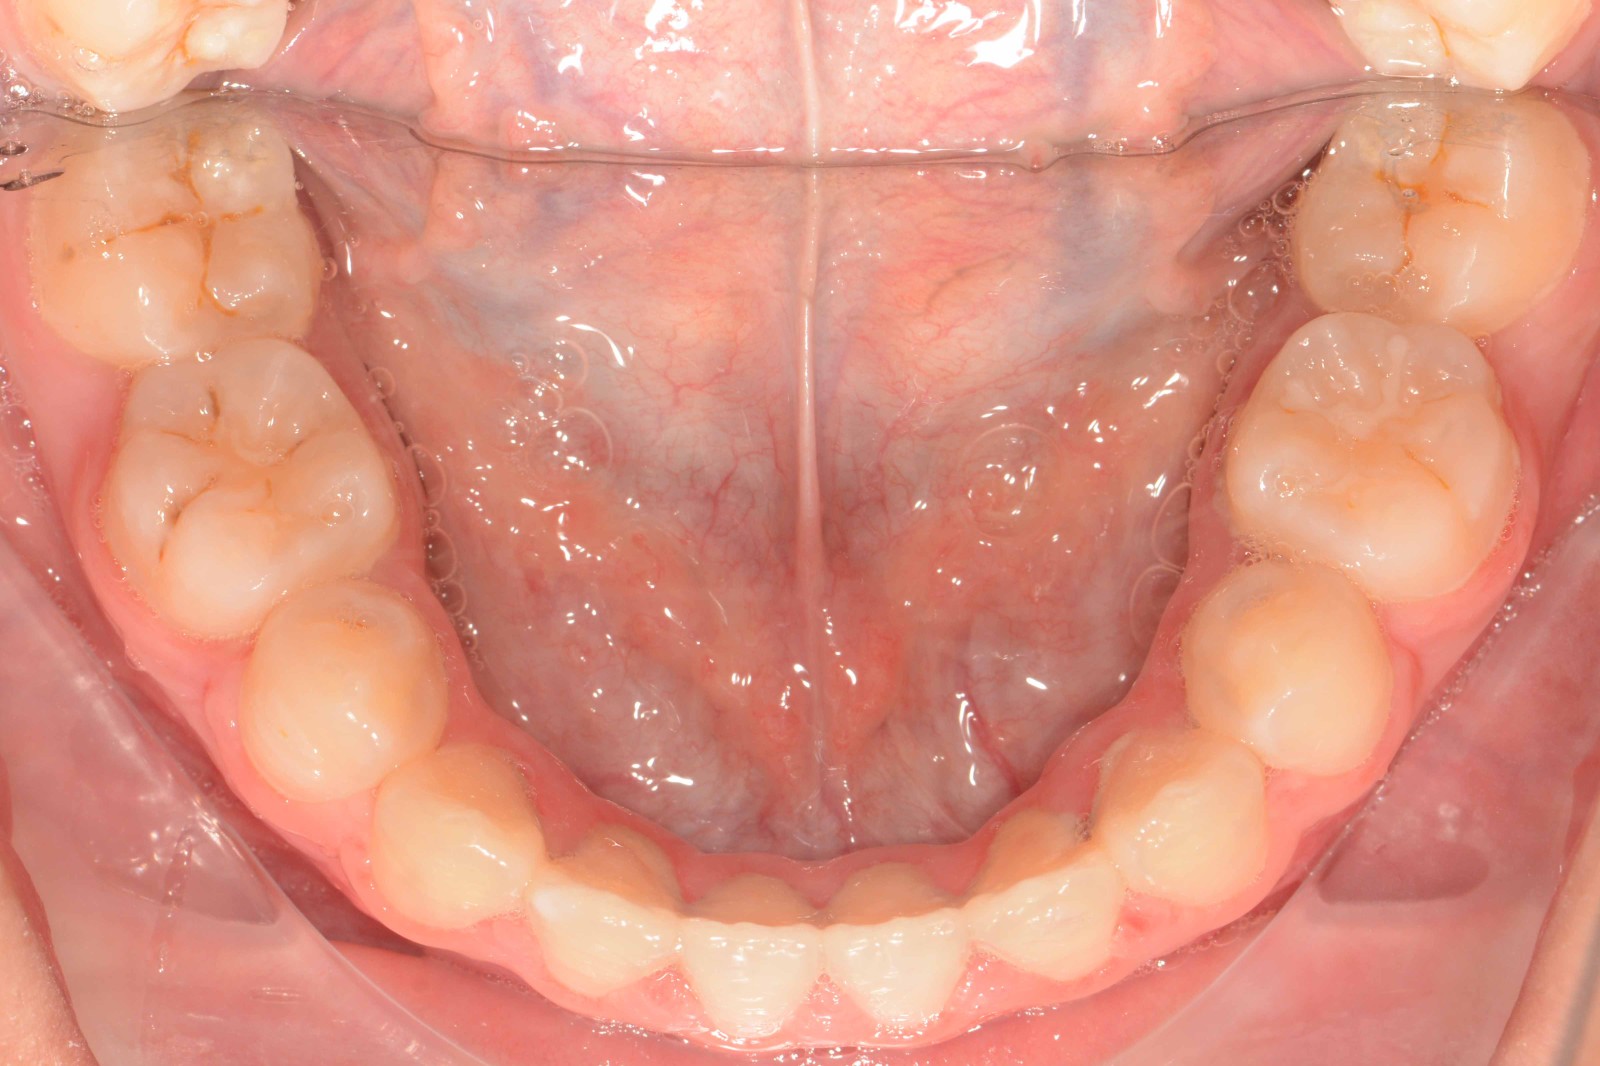

患者:14岁女性

前牙区开颌3mm

诊断:安氏II类错颌畸形  开颌

矫治后: